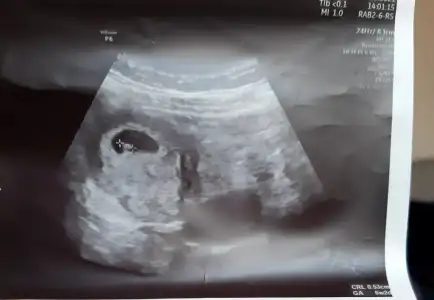

12 Kasım 2513.42 çıktı. Doktor ağrılar normal ama daha önce düşüğün olduğu için riske girmeyelim dedi iğne verdi. Vajinal ultrasonda keseyide gördük 🥰🥰 Benim miniğime bi bakın bakalım. Bir de beta hcg sanki biraz yüksek gibi sat 10 ekim 🤷 onu da anlamadım.

Eklentiler

• IMG_20211112_163255.webp

IMG_20211112_163255.webp

23 KB · Görüntüleme: 51